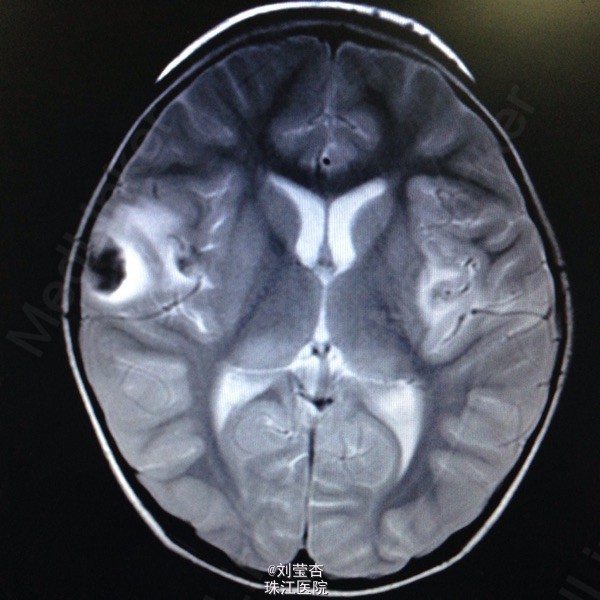

患儿女,3岁,因“咳嗽、流涕6天,发热5天,抽搐1次”入院。患儿接触家猫后出现流清涕,伴咳嗽,为间断单声咳,2天后出现发热,热峰39.5℃,予退热处理,患儿仍有反复发热,后患儿出现双眼向中上方凝视,双眼眼周肌肉抽动,伴口角流涎,无伴口周发绀、牙关紧闭,神志清楚,呼之可应,体温不详,四肢末梢温暖,四肢肌张力不高,持续约1分钟后可自行缓解。到当地医院就诊,查血常规:白细胞10.8G/L,中性粒细胞66.1%,淋巴细胞百分数27.1%,血红蛋白110g/L,血小板272 G/L,CRP4.2mg/L;胸片示支气管炎;头颅CT示右侧颞叶、双额叶多发散在脑出血。予吸氧、退热、抗感染、抗炎、补液、降颅压、止血等处理,患儿未再出现抽搐,患儿仍有反复发热,家属要求转我院进一步治疗。

查体:浅昏迷,反应一般,CRT2s,左侧耳后级颌下可触及3个肿大淋巴结,大小为0.5*0.5cm,质软,可活动,无压痛,与周围组织不粘连,双侧瞳孔等大不等圆,左侧瞳孔3mm,右侧瞳孔2.5mm,对光反射灵敏,口腔黏膜可见散在溃疡,咽部粘膜充血,双侧扁桃体Ⅰ度肿大,充血,未见黄白色脓点及分泌物,颈部稍抵抗,双肺呼吸音粗糙,可闻及大量痰鸣音,脑膜刺激症Kernig征可疑阳性,Brudzinski征可疑阳性。病毒八项:RUBE-IgG 26.8IU/Ml,CMV-IgG 117U/Ml,HSV-IgM 2.3S/CO,HSV-IgG 21.0S/CO,病毒两项:EB病毒DNA定量<5.00E+02(阳性)拷贝/mL,巨细胞病毒DNA定量9.65E+02(阳性)拷贝/mL;脑脊液常规:无色,透明,RBC 420M/L,WBC 40M/L,红细胞形态基本正常,潘氏试验(-);脑脊液单纯疱疹病毒DNA定量:单纯疱疹Ⅰ型DNA定量4.79+03(阳性)拷贝/mL,单纯疱疹Ⅱ型DNA定量低于检测下限拷贝/mL。

诊断:1.病毒性脑炎(单纯疱疹病毒感染)2.支气管肺炎。入院后予抗炎、抗病毒、抗惊厥、脱水、降颅压、促醒、输血浆,改善循环、雾化吸入、维持水电质平衡、营养支持等治疗。